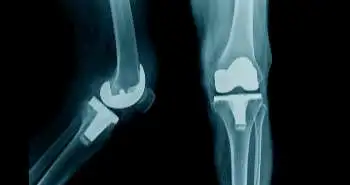

Is there any association between statin use and postoperative pain outcomes in patients who undergoes total knee arthroplasty?

Consumption of perioperative statin accompanies with enhanced postoperative opioid consumption following total knee arthroplasty executed under spinal anaesthesia, as evident from the findings of a recently published retrospective, observational study in the Journal of Regional Anesthesia & Pain Medicine.

Medical records of patients who underwent elective total knee arthroplasty under spinal anaesthesia were analyzed as inpatients in a tertiary hospital from January 2005 to October 2017. The postoperative day (POD) 3 of patients who took preoperative statins and of patients who did not receive preoperative statins were compared to assess the pain outcomes.

One thousand eighty-eight propensity-matched participants were selected for the final analysis. The patients who took statins showed a higher rate of total morphine equivalent consumption through POD 3 as compared to the non-statin group, but with comparable NRS pain scores. Although the rise in morphine consumption was minimal, therefore, its clinical significance remains debatable.